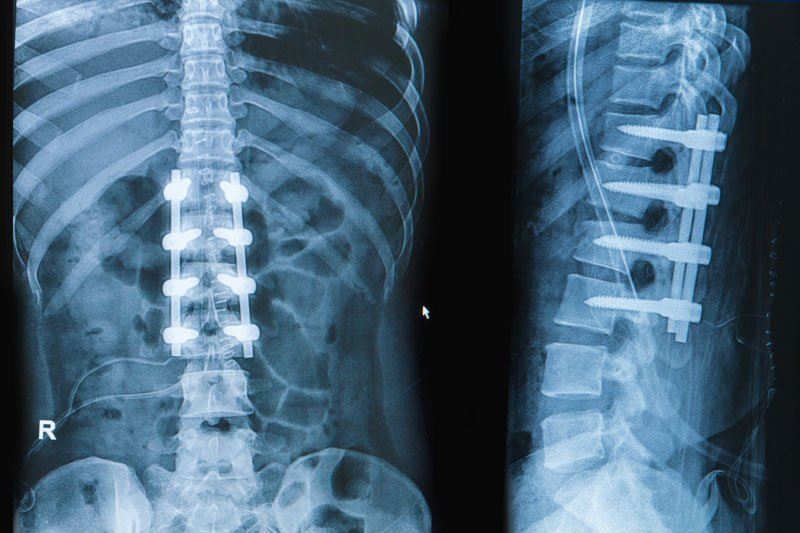

A popular treatment for spinal fractures and compression of spinal nerves, spinal fusion surgery is a procedure in which two or more spinal vertebrae are permanently joined together and stabilised with screws. In some instances, a surgeon will also recommend that bone grafts are placed in between vertebrae to add more stability.

Spinal fusion surgery is a fairly major procedure and recovery from the surgery will usually take around three months. Patients will generally be advised to avoid strenuous activity such as sports during the recovery time.